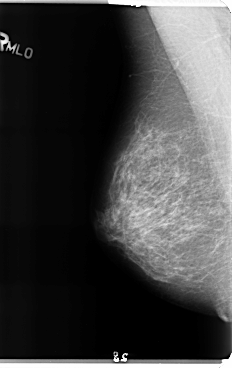

B_3158_1.LEFT_MLO

LEFT_MLO LINES 4760 PIXELS_PER_LINE 2760 BITS_PER_PIXEL 12 RESOLUTION 50 OVERLAY